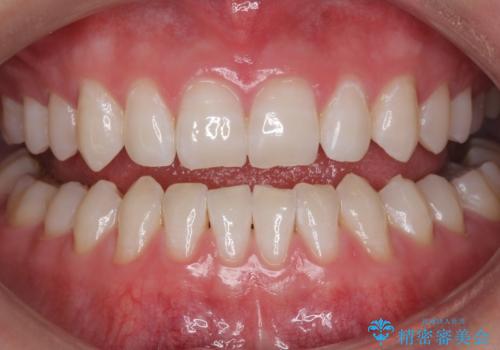

歯の表面に、茶色く色が残っている所がありますが、これは詰め物の変色の所と、虫歯になっている所です。以前に、CR(コンポジットレジン)による虫歯治療がされています。

CRは経年的劣化や、着色してしまうことがあります。PMTCでクリーニングを行うと、古いCRが目立つことがあるため、気になる際は詰め替えを行います。

茶色くなっている部分が、着色なのか、劣化なのか、虫歯によるものなのかは判別が難しいことがあります。そのため、定期的にPMTCを行うことで状態の確認が的確に行えます。

また、治療が開始される前などにも、全体的にクリーニングを行いご自身本来の歯の色、状態を精密に確認することが大切です。